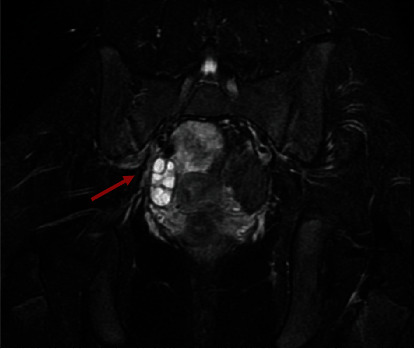

莫加尼水瘤扭转是一种罕见病,可导致年轻女性急性腹痛。我们报告了一例 13 岁女孩因急性腹痛而接受莫氏包虫病扭转治疗的病例。文献中关于 18 岁以下女性患有这种疾病的病例不到 20 例。通过我们按照 PRISMA 声明进行的系统性回顾,我们希望强调诊断的难度,以及在女性急腹症的鉴别诊断中考虑这种病变的重要性,以便及时进行手术治疗,保护这些患者的生育能力。

Torsion of the hydatid of Morgagni is a rare condition which can cause acute abdominal pain in young female. We present a case report of a 13-year-old girl with acute abdominal pain and treated for torsion of the hydatid of Morgagni. Less than 20 cases of female younger than 18 years old with this condition are been described in the literature. Through our systematic review performed following the PRISMA statement, we want to emphasize the difficulty in diagnosis and the importance of considering this pathology in the differential diagnosis of acute abdomen in females with the aim of obtaining a timely surgical treatment to preserve fertility in these patients.